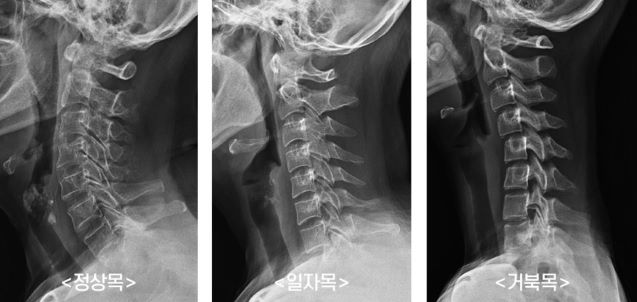

정상적인 사람이라면 목뼈를 측면에서 봤을 때 C자 모양의 커브를 형성하고 있으며 이를 의학적으로 경추 전만곡이라고 합니다. 그러나 수없이 많은 원인으로 인하여 전만곡이 감소하여 목뼈의 형태가 일자형이 되거나 오히려 앞으로 기울어져 역 C자 형태로 변형되는 경우를 흔히 우리는 거북목이라고 부릅니다.